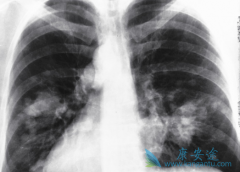

为了评估EGFR突变阳性NSCLC患者一线 厄洛替尼 (GRLONAT)疗法可靠有效性,以及疾病发生进展后厄洛替尼疗法的治疗效果,Keunchil Park教授等开展了一项开放性单组II期临床研究——ASPIRATION研究项目。研究人员纳入2011年-2012年间,涵盖香港、韩国、台 ...